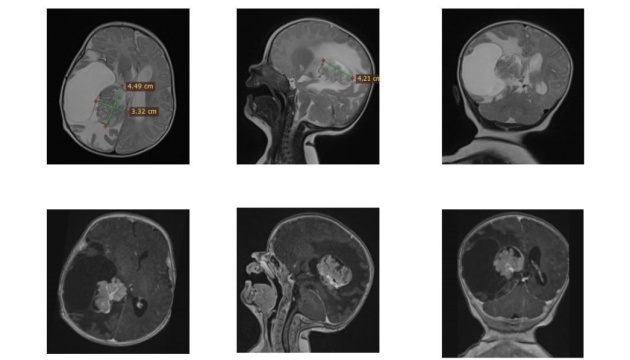

Зазначається, що у двомісячної дитини з Рівного утворилася небезпечна пухлина у правому боковому шлуночку мозку, яка загрожувала її життю. Єдиним шансом врятувати немовля було складне нейрохірургічне втручання.

«Видалення пухлини у такої малесенької пацієнтки саме по собі є надзвичайно ризикованим. Утворення розташовувалося в зоні судинного сплетення з високим кровопостачанням, а отже, з високим ризиком значної крововтрати. До того ж пухлина була близько до ділянки, відповідальної за рухи. Тому операція вимагала максимальної точності та ретельної підготовки», - зауважив керівник Клініки дитячої нейрохірургії Михайло Ловга.

Саме втручання тривало довше, ніж зазвичай: лікарям доводилося поетапно зупинятися, контролюючи крововтрату, та надзвичайно обережно видаляти утвір, щоб не пошкодити рухові зони мозку. Попри це, операція пройшла успішно. Життя дитини поза загрозою.